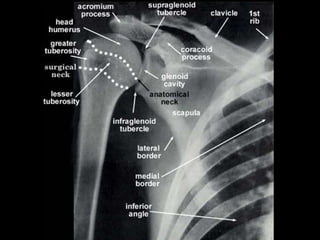

Anatomy

• Osteology

– anatomic neck (epiphyseal plate)

– surgical neck (weakened area)

• Vascular anatomy

– anterior humeral circumflex artery

– posterior humeral circumflex artery

Anatomy • Osteology – anatomicneck (epiphyseal plate) – surgical neck (weakened area)

Anatomy • Vascular anatomy –anterior humeral circumflex artery – posterior humeral circumflex artery